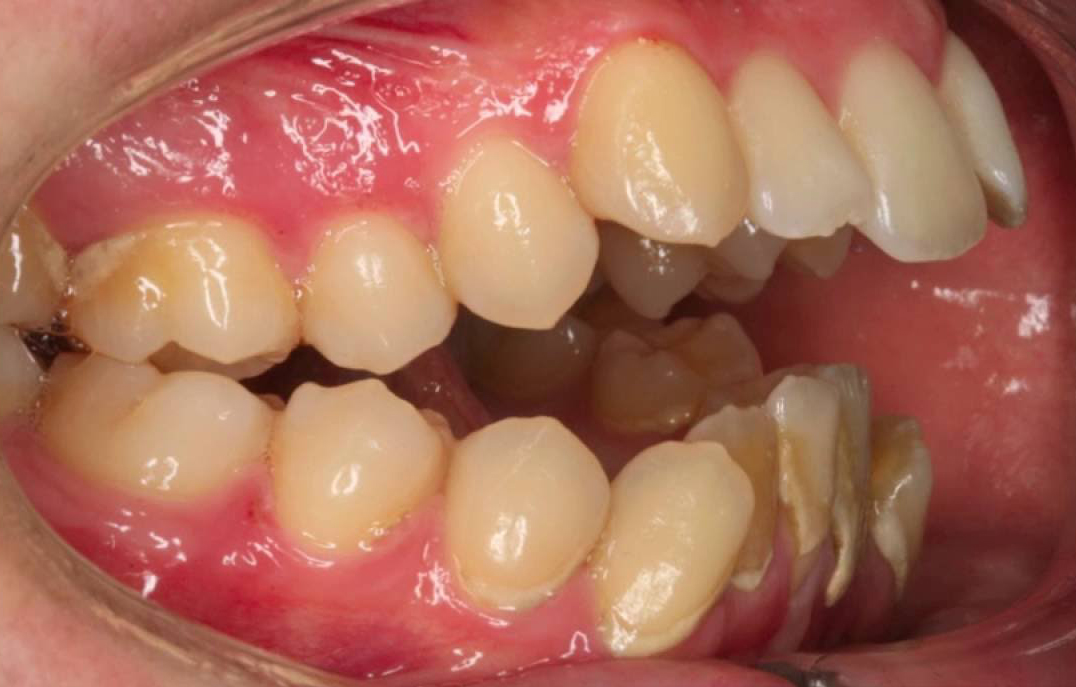

WebA nivel profesional, se conoce como “oclusión perfecta” o mordida de “Clase I”. Este tipo de mordida es la que presenta una alineación total de los dientes y para ello. WebCómo corregir una mala mordida y lucir una sonrisa alineada. En la corrección de una mala mordida, la ortodoncia y el uso de brackets es el. WebMordida Protrusiva o Protrusión Dental. Se debe a una maloclusión de Clase II. Es la mordida en la que los dientes de alguna o ambas arcadas, normalmente los. WebComo hemos explicado anteriormente, la mordida abierta se produce por un incorrecto crecimiento de los dientes y los huesos maxilares. Los aparatos utilizados en. WebEn la mordida abierta, los dientes superiores e inferiores no se encuentran en su posición correcta al morder. Esto puede ocurrir en la parte delantera o trasera de.

WebMordida Protrusiva o Protrusión Dental. Se debe a una maloclusión de Clase II. Es la mordida en la que los dientes de alguna o ambas arcadas, normalmente los. WebComo hemos explicado anteriormente, la mordida abierta se produce por un incorrecto crecimiento de los dientes y los huesos maxilares. Los aparatos utilizados en. WebEn la mordida abierta, los dientes superiores e inferiores no se encuentran en su posición correcta al morder. Esto puede ocurrir en la parte delantera o trasera de. WebTener una mordida correcta es un factor muy importante para poder disponer de una buena salud bucodental. Y no solo eso, también es importante porque,. WebPara tener una mordida correcta u oclusión correcta, se debe tener en cuenta otros factores o detalles que te mencionamos a continuación: Se debe observar. WebUna correcta oclusión es la conocida como mordida de Clase I. Es en ésta mordida en la cual están alineadas prácticamente con exactitud todas las piezas dentarios, es decir,. WebLa mordida abierta es un tipo de maloclusión que se da cuando los dientes de arriba no logran entrar en contacto con los de abajo, impidiendo el cierre completo de. Web-CLASE I (MORDIDA CORRECTA): significa que el canino inferior muerde (3-4mm)por delante del canino superior, es decir, los dientes a la perfección como si. WebEn la clase I, considerada la ideal, los molares están alineados y engranan perfectamente. En la clase III el primer molar inferior pasa por delante del.